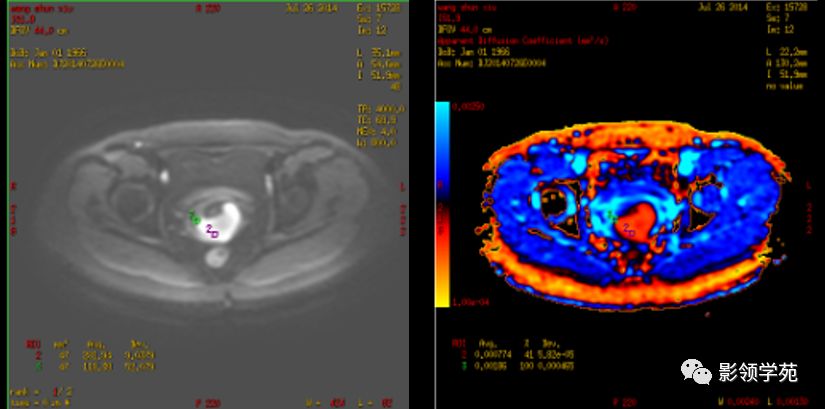

- 新技术:DWI

磁共振扩散加权成像,DWI

DWI是目前唯一能在活体观察组织水分子微观运动的无创性影像学方法,可以检测出与组织含水量变化相关的形态学和生理学早期改变,并以表观扩散系数(ADC)值来量化表示。

DWI:局限性高信号,癌组织ADC值<癌旁组织<小于正常宫颈组织

宫颈癌术后复发患者,DWI上病灶较T2 fs及T1+C更加明显

DWI显示淋巴结肿大